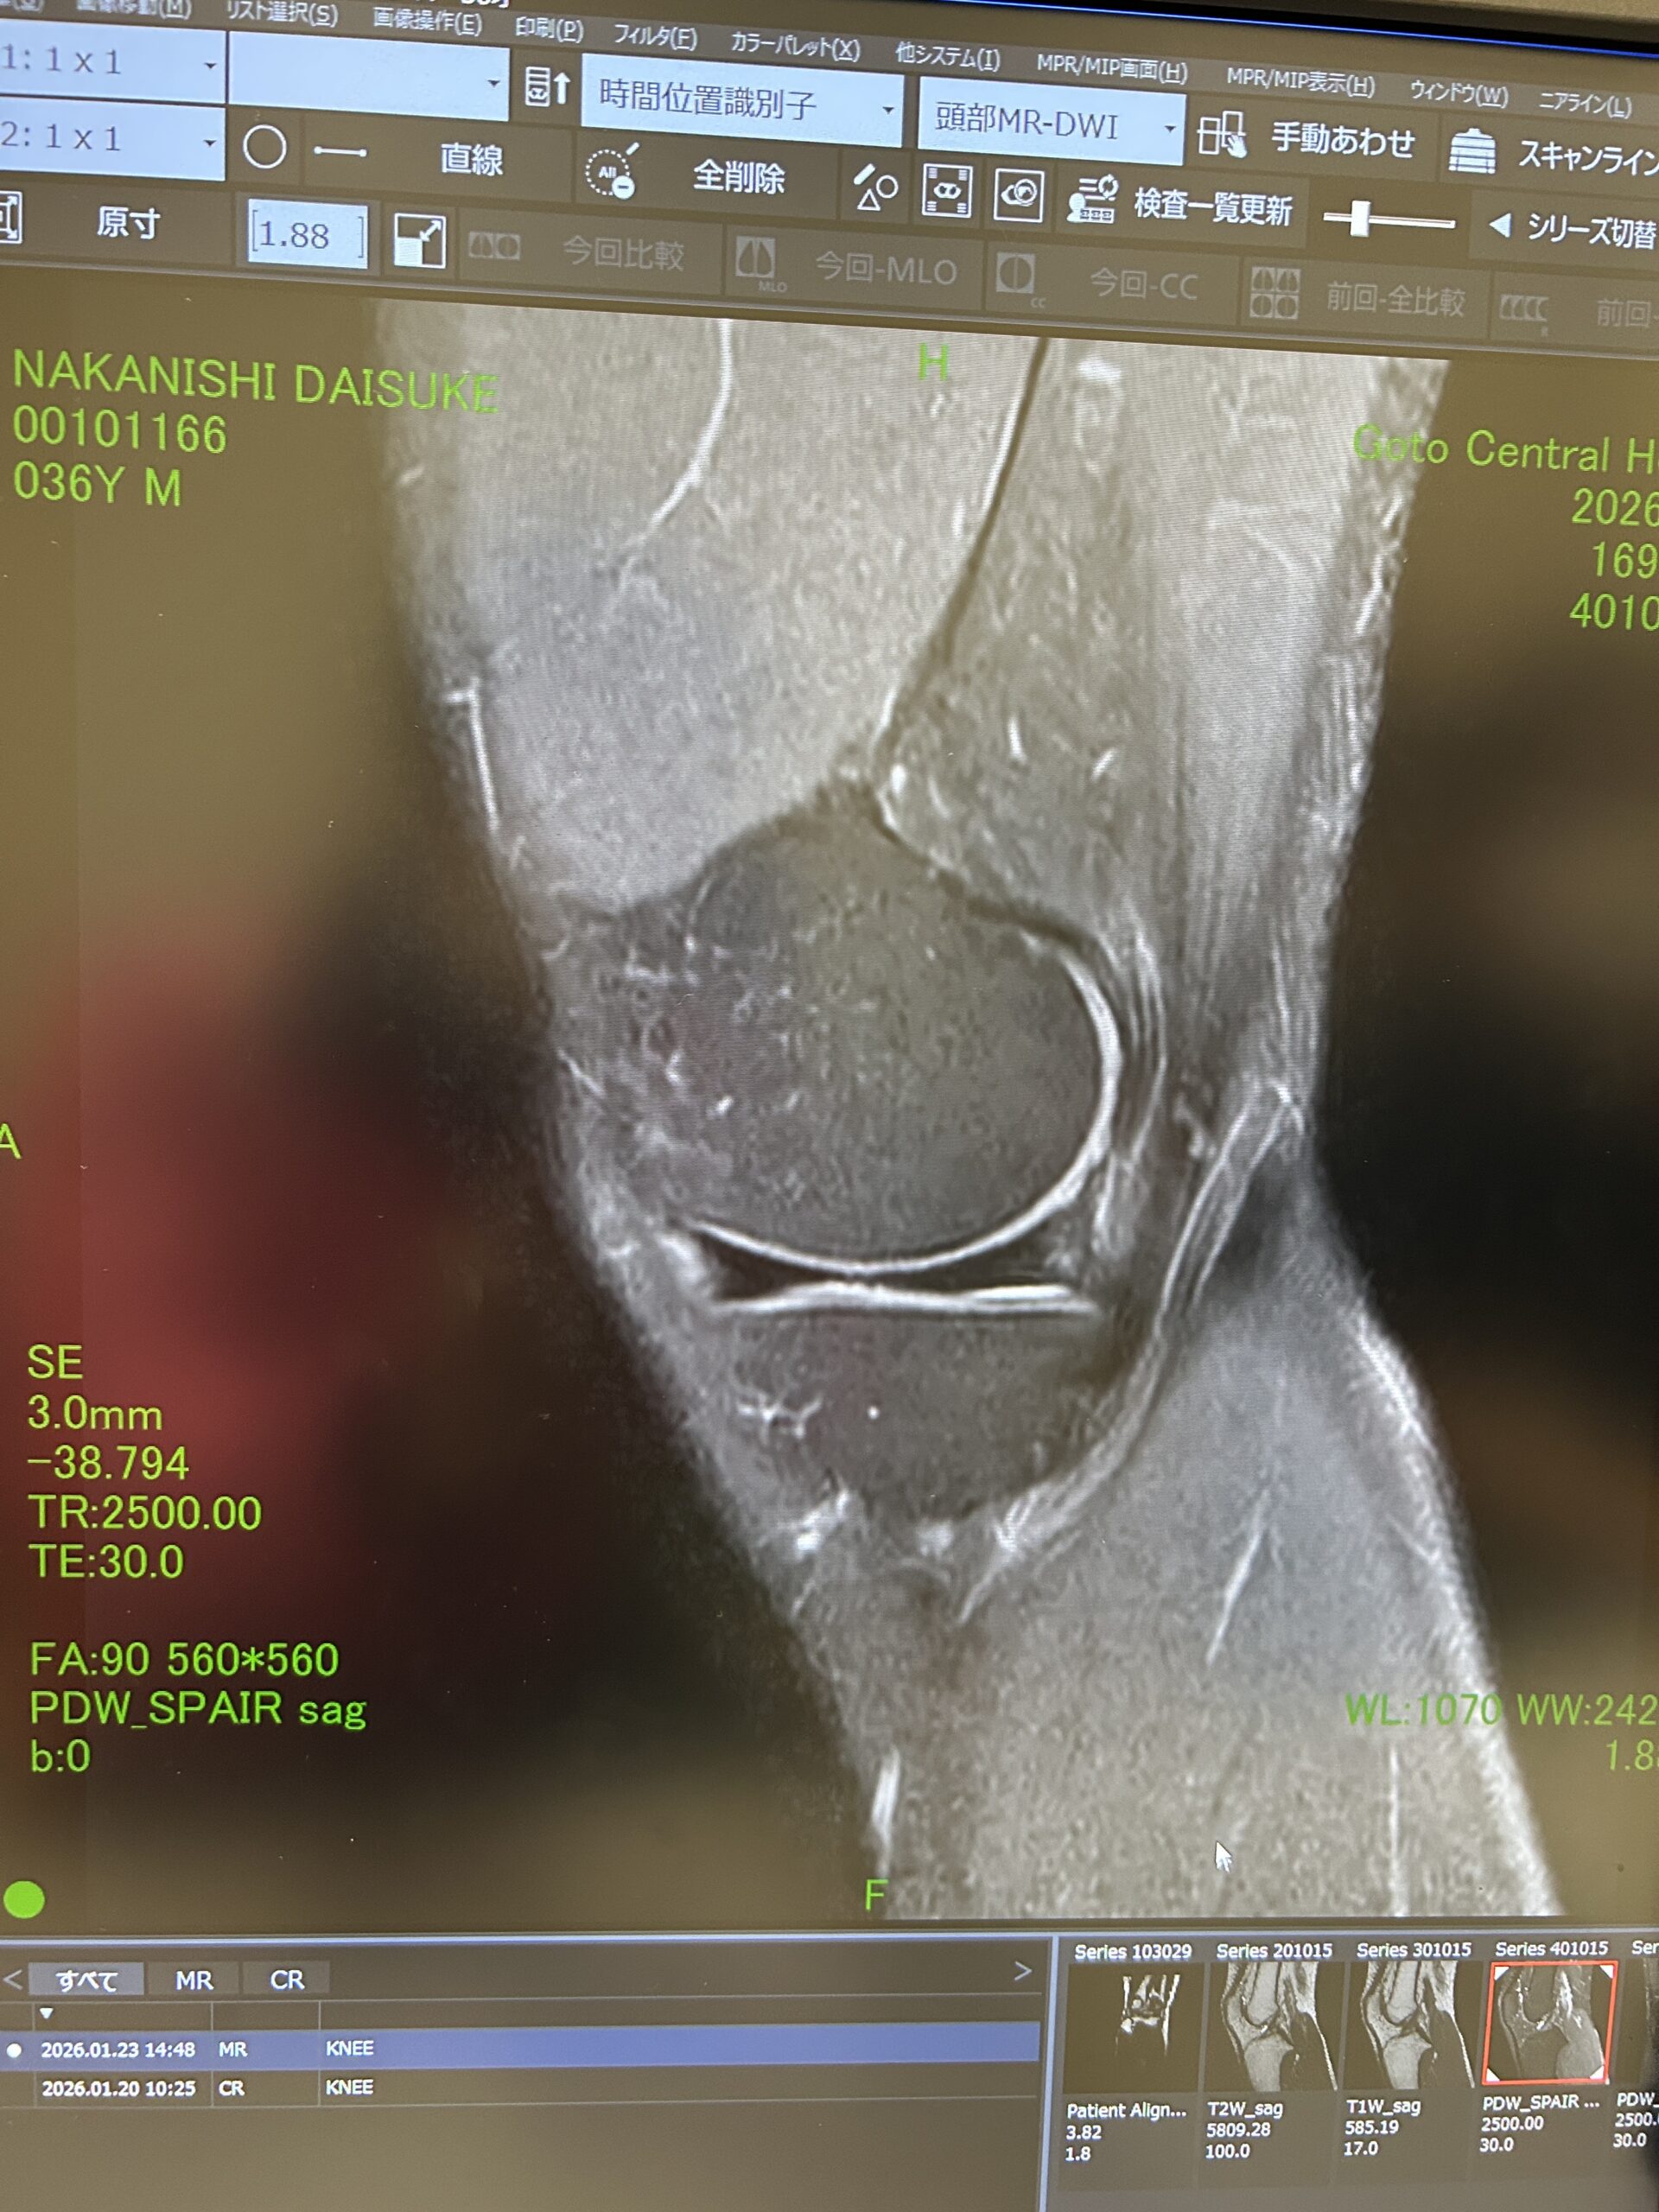

最初はランナー膝かなと思っていましたが、中々回復が遅かったので1月に五島病院でMRIを取って頂きました。

その結果、円盤状半月板という事が分かりました。